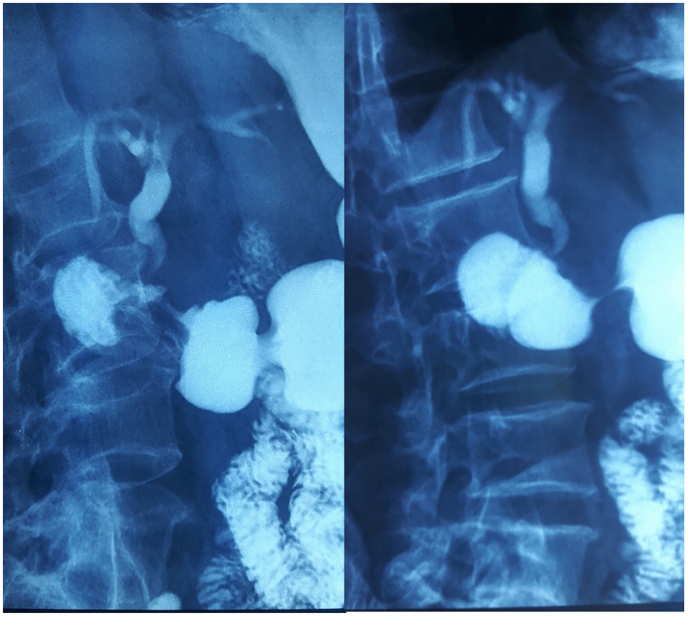

The diagnosis of distal CBD cholangiocarcinoma was suspected and tumor markers (Ca 19-9 and ACE) were done but were negative. An echo endoscopy was attempted to confirm the malignant nature of the CBD stricture but it was not possible due to a duodenal stenosis. The patient was reinterrogated and revealed a history of ulcer-like abdominal pain that has been ongoing for ten years. Duodenal biopsy was negative for malignant cells but positive for H. pylori bacteria. We reviewed the Cholangio-MRI and we noticed that the CBD had a hook shaped distal portion. Peptic ulcer stenosis complicated with distal CBD retraction and choledochoduodenal fistula was then suspected. Barium study showed normal passage in the small bowel but an unusual passage in the biliary ducts revealing a hook-shaped distal CBD (Fig. 2). The patient was put on proton pump inhibitors and antibiotics with favorable evolution: regression of jaundice and resolution of the abdominal pain and vomiting.

Diagnostic tools play a crucial role in identifying choledoco-duodenal fistulas. Imaging studies are particularly useful. Pneumobilia, the presence of air within the bile ducts, is a significant radiographic marker found in approximately 50 % of cases. This can be detected on abdominal X-rays or computed tomography (CT) scans [ref. 4]. Another useful diagnostic method is the upper gastrointestinal (GI) barium series, where the passage of contrast material into the bile ducts can be observed, confirming the presence of a fistula [ref. 1].